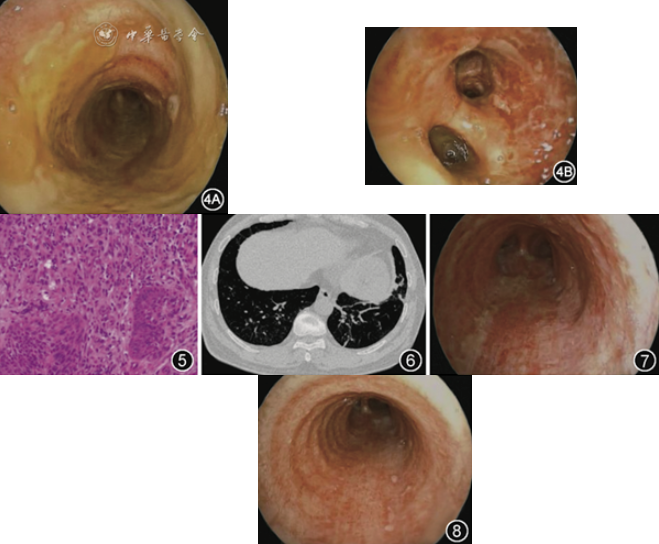

患者男,50岁,因“咳嗽、咳痰、发热1周,咯血1 d”于2024年2月10日入院。患者1周前受凉后出现咳嗽,咳黄白痰,间断发热4 d,体温最高38.6 ℃,伴畏寒、鼻塞、流涕,自服“阿奇霉素、布洛芬”治疗,效果差。1 d前剧烈咳嗽时出现痰中带血,19 h前突发咯鲜血,量约50 ml,于当地县人民医院行胸部CT平扫未见异常(图1)。7 h前行计算机断层扫描肺动脉造影(computed tomography pulmonary angiogram,CTPA)未见肺动脉栓塞征象,双肺下叶见多发斑片影(图2)。遂转入我院急诊,复查胸部CT平扫示双肺多发斑片高密度影(图3),给予垂体后叶素止血治疗后收入院。患者既往体健,否认吸烟、饮酒史。

图1 2024年2月9日患者入院前19 h胸部CT平扫未见异常

图2 2024年2月9日患者入院前7 h行CTPA未见肺动脉栓塞征象,双肺下叶见多发斑片影

图3 2024年2月10日复查胸部CT平扫示双肺下叶多发高密度影

术后患者指氧饱和度为90%(鼻导管吸氧4 L/min),阵发性剧咳和憋气,无声音嘶哑,2024年2月17日行支气管镜检查,镜下见喉部黏膜充血,未见坏死,声门开合良好。气管支气管黏膜弥漫覆盖黄色脓性假膜,部分黏膜糜烂坏死;右肺下叶背段开口明显狭窄,黏膜粗糙,无糜烂坏死,行支气管黏膜活检;左肺下叶黏膜严重坏死,见多发溃疡,行支气管肺泡灌洗,灌洗液为黄色,量50 ml(图4)。肺泡灌洗液mNGS仅检测出金葡菌,序列数为6 300(lukF-PV 序列数4)。肺泡灌洗液涂片查见革兰阳性球菌,细菌+真菌培养阴性,抗酸染色阴性,肺泡灌洗液GM试验<0.1 S/CO。支气管黏膜病理示重度急性炎症(图5)。改用利奈唑胺(600 mg,1次/12 h,静脉滴注)抗感染治疗,治疗5 d后,指氧饱和度为94%(未吸氧),复查胸部CT平扫示双肺多发斑片状阴影吸收(图6),第6 d复查支气管镜见气道内黏膜较前好转,可见较多分泌物并给予吸引(图7),第9天复查支气管镜,气道内黏膜较前进一步好转(图8)。

图6 2024年2月23日利奈唑胺治疗5 d后复查胸部CT平扫示双肺下叶多发斑片影基本吸收